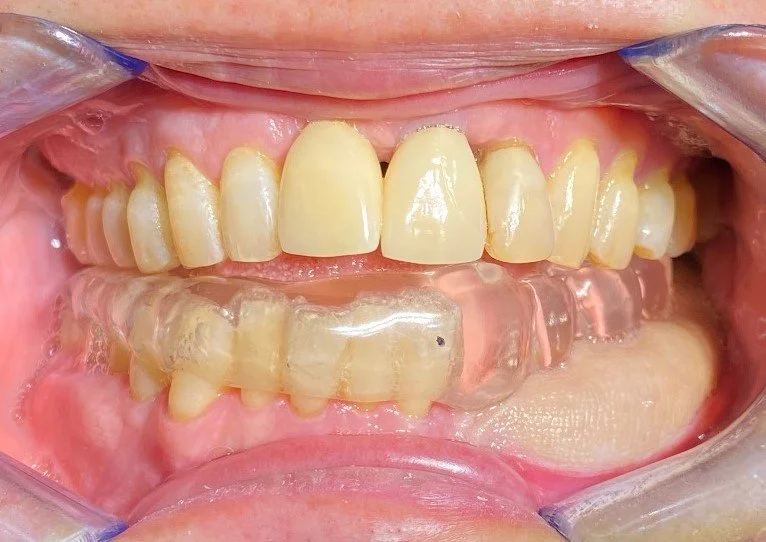

The remaining lower 6 front teeth that were deemed to have insufficient bone for longevity and unsuitable for a bite reconstruction, these teeth were extracted.

The removeable implant denture in place with a normal overbite and the decay removed and fillings placed.